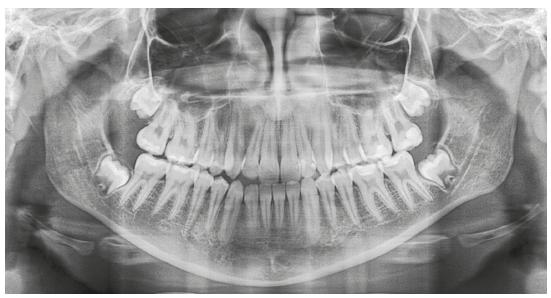

La deficiencia transversal del maxilar es una de las anomalías esqueléticas más frecuentes de los arcos dentarios. Puede ir acompañada por mordida cruzada posterior y apiñamiento dental Es una condición progresiva que tiende a aumentar en personas jóvenes y cerca del 30% de pacientes ortodóncicos adultos presentan una deficiencia transversal del maxilar y una mordida cruzada posterior.

La Expansión Palatina Rápida Convencional (en inglés Rapid Palatal Expansión, RPE) ha demostrado ser un método de tratamiento confiable para corregir la desarmonía esquelética transversal del maxilar en pacientes prepuberales , sin embargo, en pacientes adultos ha sido considerada imposible o rara vez exitosa debido a que en la adolescencia tardía, la sutura media del paladar y las articulaciones adyacentes empiezan a fusionarse y se vuelven más rígidas por lo que en adultos tiene poco o ningún efecto esquelético y se han descrito efectos dentoalveolares y periodontales perjudiciales. -señaló la experta en ortodoncia y ortopedia dentofacial, que brinda en la ciudad de Mérida sus servicios de Ortodoncia, Ortopedia dentofacial, Tratamientos ortopédicos en niños, Tratamientos ortodónticos, Problemas de la mandíbula y bucales, Vértigo, Migraña, Ronquido, Ortopedia funcional, Medicamentos, Desalineación dental, Tratamiento de ortodoncia sin brackets y con brackets (metálicos o estéticos).

La Expansión Palatina Rápida Asistida en forma Quirúrgica (en inglés Surgically assisted RPE, SARPE) es un tratamiento a elección para la deficiencia transversal del maxilar en adultos jóvenes. -agregó la Dra. Mónica Souza Paz.

Sin embargo, debido a la poca adherencia a tratamientos quirúrgicos complejos y al aumento de la demanda por tratamientos no quirúrgicos se introduce la Expansión Palatina Rápida Asistida por Microimplantes o MARPE que es una técnica de expansión rápida palatina asistida por micro tornillos que puede ser empleado en pacientes adultos jóvenes para abrir la sutura palatina media, corregir la deficiencia transversal del maxilar en pacientes adultos y para maximizar la separación ortopédica del maxilar. MARPE incorpora los microtornillos anclados al paladar para asegurar expansión del hueso y la separación de las estructuras óseas durante el periodo de consolidación. Revisemos entonces como se realiza un tratamiento con estos procedimientos. –concluyó la dentista especialista en ortodoncia y ortopedia dentofacial.